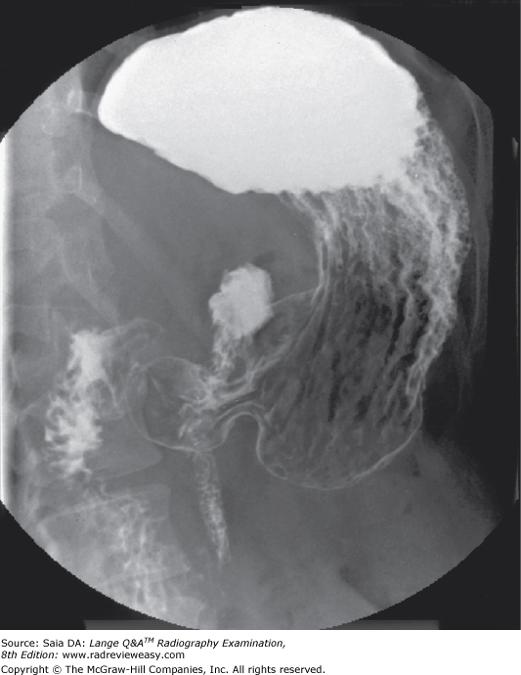

The radiograph pictured in Figure A may be used to evaluate

1. polypoid lesions.

2. the lateral wall of the descending colon.

3. the posterior wall of the rectum.

1 and 2 only

The image shown in Figure 7–4 was made in the following recumbent position

LPO